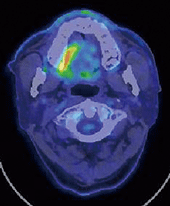

PET-CTでは右側口蓋部および頸部にFDGの異常集積を認めた(図❷)。画像検査後に行った生検で悪性黒色腫と診断されたので、治療は高次医療機関に依頼したが、受診は中断され、以後の経過は不明となった。

図❷ PET-CT像